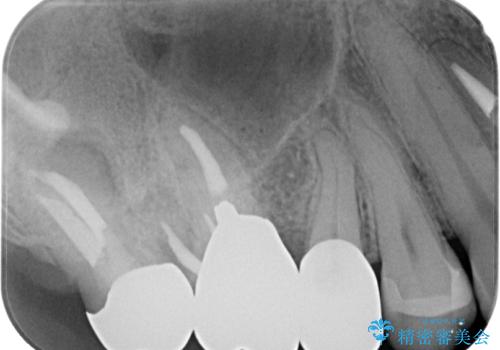

歯の形態や咬み合わせが正確に反映されるように、シリコーンゴムによる精密な型どりを行いました。

完成したセラミックインレーは精度が高く、適合性に優れているため、歯と調和した自然な仕上がりとなります。

適合の良い詰め物は、二次齲蝕のリスクが低いです。